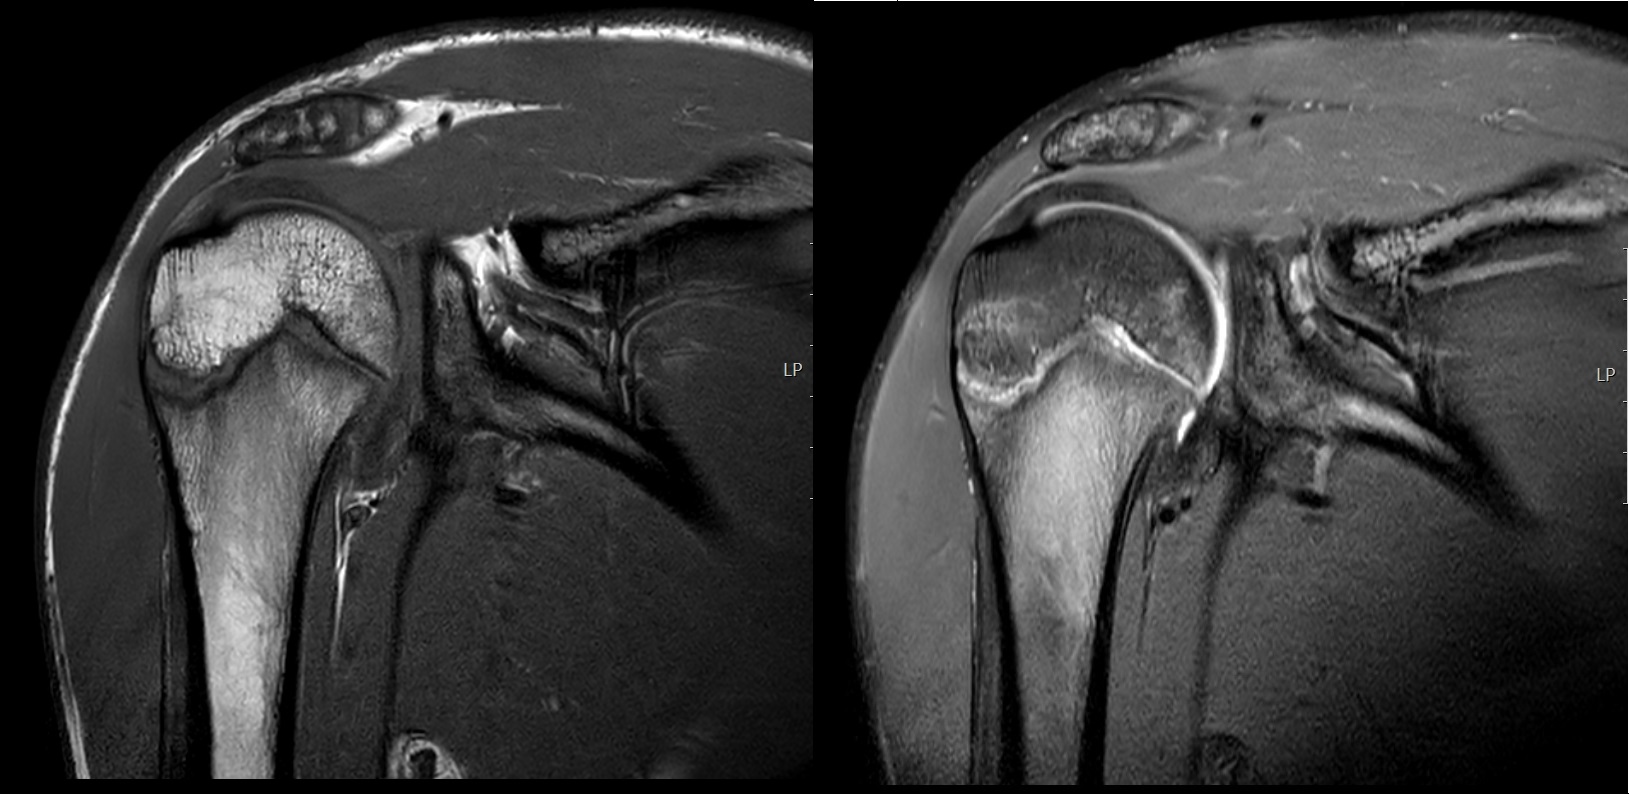

Clinicians must suspect periphyseal stress injuries when pain localizes around a growth plate. Radiographs are the first-line screening imaging modality that may show physeal widening, irregularity, and fragmentation, and clinicians use them to exclude alternative diagnoses. Magnetic resonance imaging is the gold standard for early detection, demonstrating bone marrow edema, physeal widening, with increased signal intensity and interruption of the zone of provisional calcification on the metaphyseal side of the physis (see figure 1)(15,16). These represent reversible stress-related changes rather than acute Salter–Harris fractures.

Coronal T1-weighted (left) and PD SPAIR (right) images demonstrate widening of the proximal humeral physis with associated fluid signal and surrounding bone marrow edema.

Across both patterns, MRI remains the most sensitive modality, with ultrasound and X-ray serving as useful adjuncts for superficial apophyseal lesions(17).